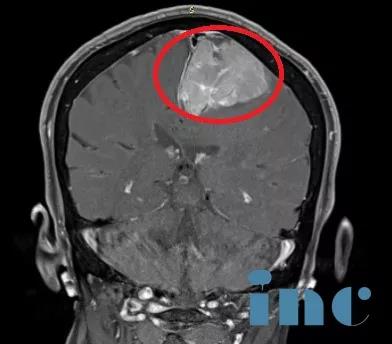

臨床診斷:左側(cè)額部大腦鐮旁腦膜瘤。

術(shù)前影像資料:左側(cè)大腦鐮旁巨大腦膜瘤,鈣化和瘤周壓迫、水腫效應(yīng)明顯。